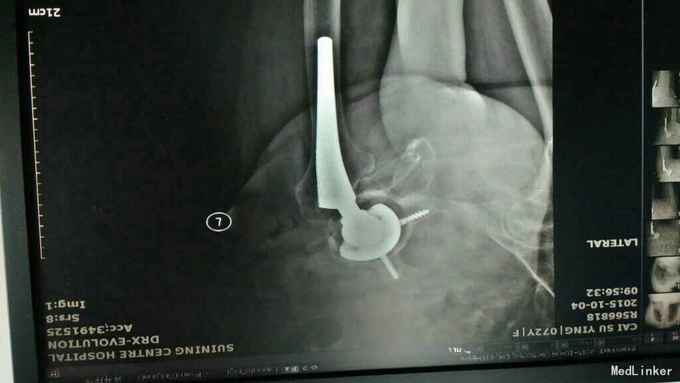

主诉:左髋关节置换术后疼痛活动受限3年 病史:3年前患者因左股骨颈骨折在当地县医院就诊,诊断明确后行全髋关节置换术,术前正常出院。出院后即感左髋关节疼痛不适,活动疼痛加重,休息缓解,疼痛位于腹股沟明显。反复于当地医院及成都等医院就诊,诊断不明确,考虑有金属过敏可能。4天前患者疼痛加重,活动进一步受限,无关节红肿,无肿胀,无畏寒发热,无其他关节疼痛。为进一步治疗收入我科。 患病以来。精神食欲可,体力下降。

查体:轮椅推入,左髋关节后外侧见10cm手术切口瘢痕,双侧腹股沟压痛,双侧大转子叩痛,双髋关节活动受限,4字实验(+),双下肢肌力3级。左乱关节屈曲90度,旋转不能。左下肢纵向叩痛(+)。 辅助检查:彩超示脂肪肝。x线腰椎骨质疏松,压缩性骨折。ESR 38,CRP 12。 影像学如下:

诊断:左髋关节置换术后假体松动; 右侧股骨头缺血坏死; 重度骨质疏松症 高血压病 压缩性骨折 治疗:左髋关节翻修术。(植骨、钛网骨水泥杯,骨水泥柄或翻修长柄MP(Link))

术中见骨质疏松明显,股骨劈裂,捆扎带固定。 术后股骨是否好愈合?